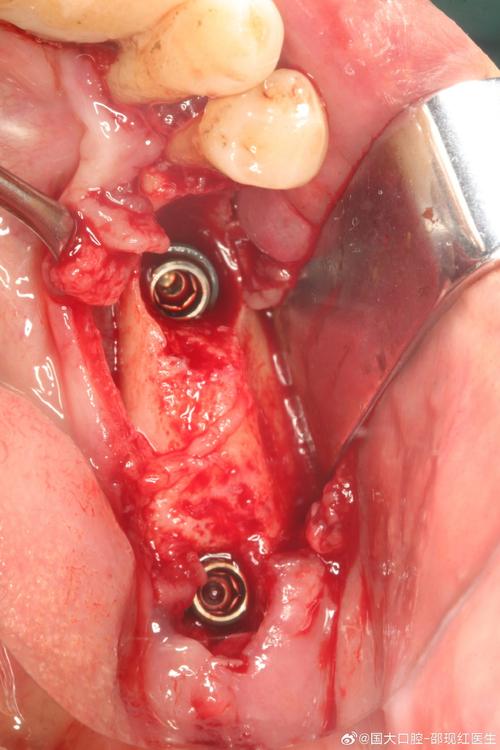

- 麻醉与切口:局部浸润麻醉或全身麻醉,根据缺损部位选择切口(如牙槽嵴顶切口、梯形切口),充分暴露骨缺损区;

- 骨床预备:去除骨缺损区的软组织、瘢痕组织,用球钻或超声骨刀制备新鲜出血的骨面,促进移植材料与宿主骨的接触;

- 植骨材料处理与植入:根据材料类型进行预处理(如自体骨需磨碎成颗粒状,人工骨需与血液混合),分层填塞骨缺损区,避免遗留死腔;

- 屏障膜覆盖:对于引导骨再生(GBR)技术,需采用胶原膜或钛膜覆盖植骨区,防止软组织长入,为骨细胞生长提供空间;

- 缝合与固定:采用可吸收缝线严密缝合,必要时使用钛钉或钛板固定骨块。